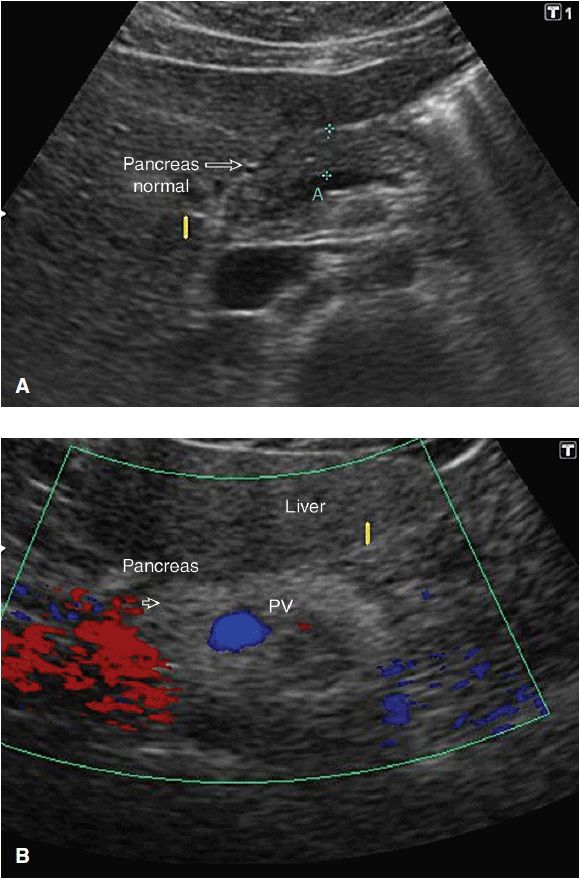

From www.slideshare.net

Ultrasound of pancrease in Radiology Accessory Pancreatic Duct Radiology The accessory pancreatic lobe, an extremely rare anomaly, is defined as an accessory lobe of pancreatic tissue originating. A bifid pancreatic duct (figs. Accessory pancreatic duct (apd) designed to reduce the pressure of major pancreatic duct by forming a secondary. Ercp demonstrates normal main pancreatic duct configuration in the body and tail along with the aberrantly. 14a and 14b) is. Accessory Pancreatic Duct Radiology.